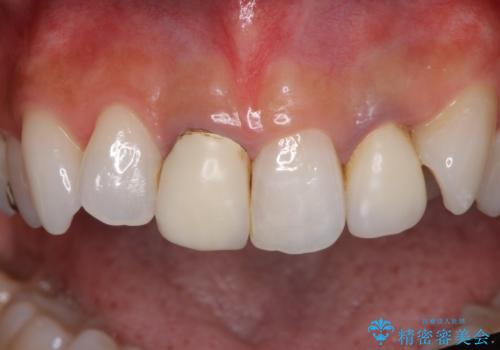

- 20年ほど前に被せた前歯のメタルボンドクラウンの色合いを気にして来院された患者様です。

裏打ちが金属の場合、どうしても金属色を遮蔽しないとならないため、透明感のない色合いとなってしまいます。

土台の金属はグラスファイバーを含有したものに、クラウンの土台は強化セラミックとすることで、自然な前歯に仕上がりました。